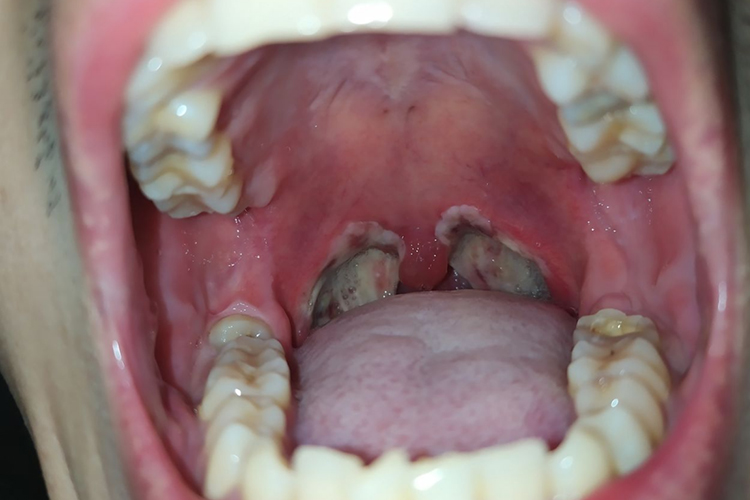

扁桃体摘除术后6小时伤口即有白膜形成,术后第二天扁桃体窝已完全覆盖白膜,术后10天内逐渐脱落。大概半个月可以完全脱落,伤口逐渐恢复。